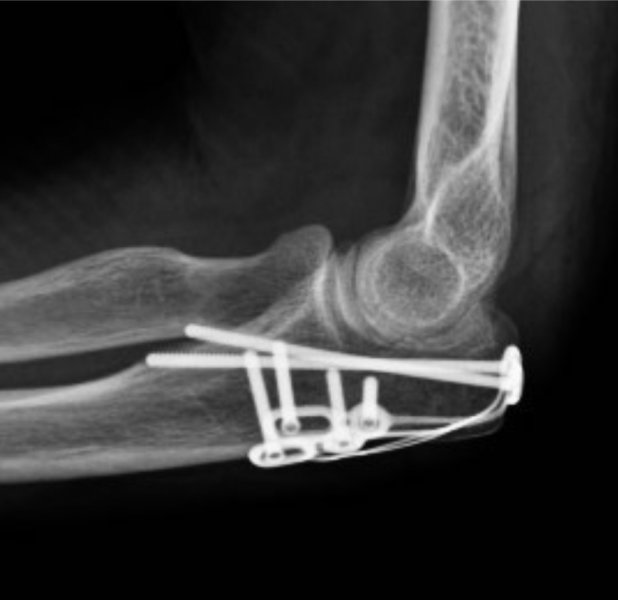

Fracture Fixation

Fracture fixation stabilizes extremely misaligned broken bones by “re-setting,” or “reduction,” by using splints, casts, and implants

A fracture is a break in a bone. This may result in deformity and pain. In addition, some fractures are known to have poor healing rates (a non-union). Because of these, modern fracture treatment often consists of ‘internal fixation’ which means fixation using plates, screws or nails which are inside the body (as opposed to external fixation which is pins or wires outside the body). As some fractures may result in deformity, poor function or post traumatic degeneration, your surgeon may recommend fixation. While some fractures may heal in a plaster or sling, there can be pain for several weeks while the fracture is unstable and fixing these allows earlier return to function and patients may elect to have treatment by internal fixation for this reason.

While the patient is under anaesthesia, cuts are made in the skin and a surgical approach through or between muscles used to gain access to the fracture. The fracture is aligned then fixation appropriate to the fracture used to stabilise the bone

• Plate and screw constructs

• Wires